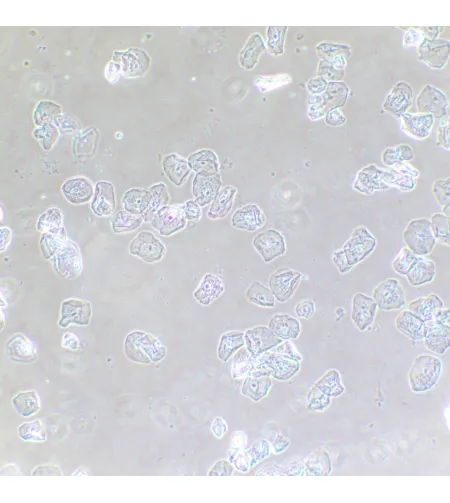

MAGUS SPH2 faasikontrastsuseadme koosneb faasikontrasti liugurite komplektist, faasikohustusega andurite komplektist ning keskendava teleskoobist. Faasikontrastsuseadet kasutatakse läbipaistvate madala kontrastsusega proovide uurimiseks, mis pole heledas väljavalguses nähtavad. Värvimine tapab elusaid rakke. Tehnika peamine eelis on see, et seda saab kasutada elusate värvimata organismide uurimiseks nende loomulikus olekus. Tehnikat kasutatakse meditsiinis, ökoloogias, farmakoloogias, põllumajanduses jne.